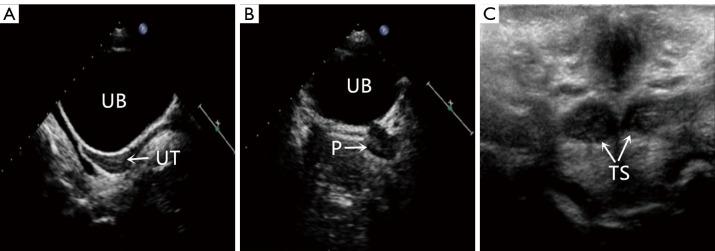

Dilated cardiomyopathy, extensive subendocardial fibrosis and myocardial non-compaction in a patient with sex development disorder: a rare case of myelin regulatory factor-related cardiac-urogenital syndrome.

Department of Radiology, Wuhan Asian Heart Hospital, Wuhan, China.

Quant Imaging Med Surg. 2025 Aug 1;15(8):7650-7655. doi: 10.21037/qims-2024-2728. Epub 2025 Jul 30.